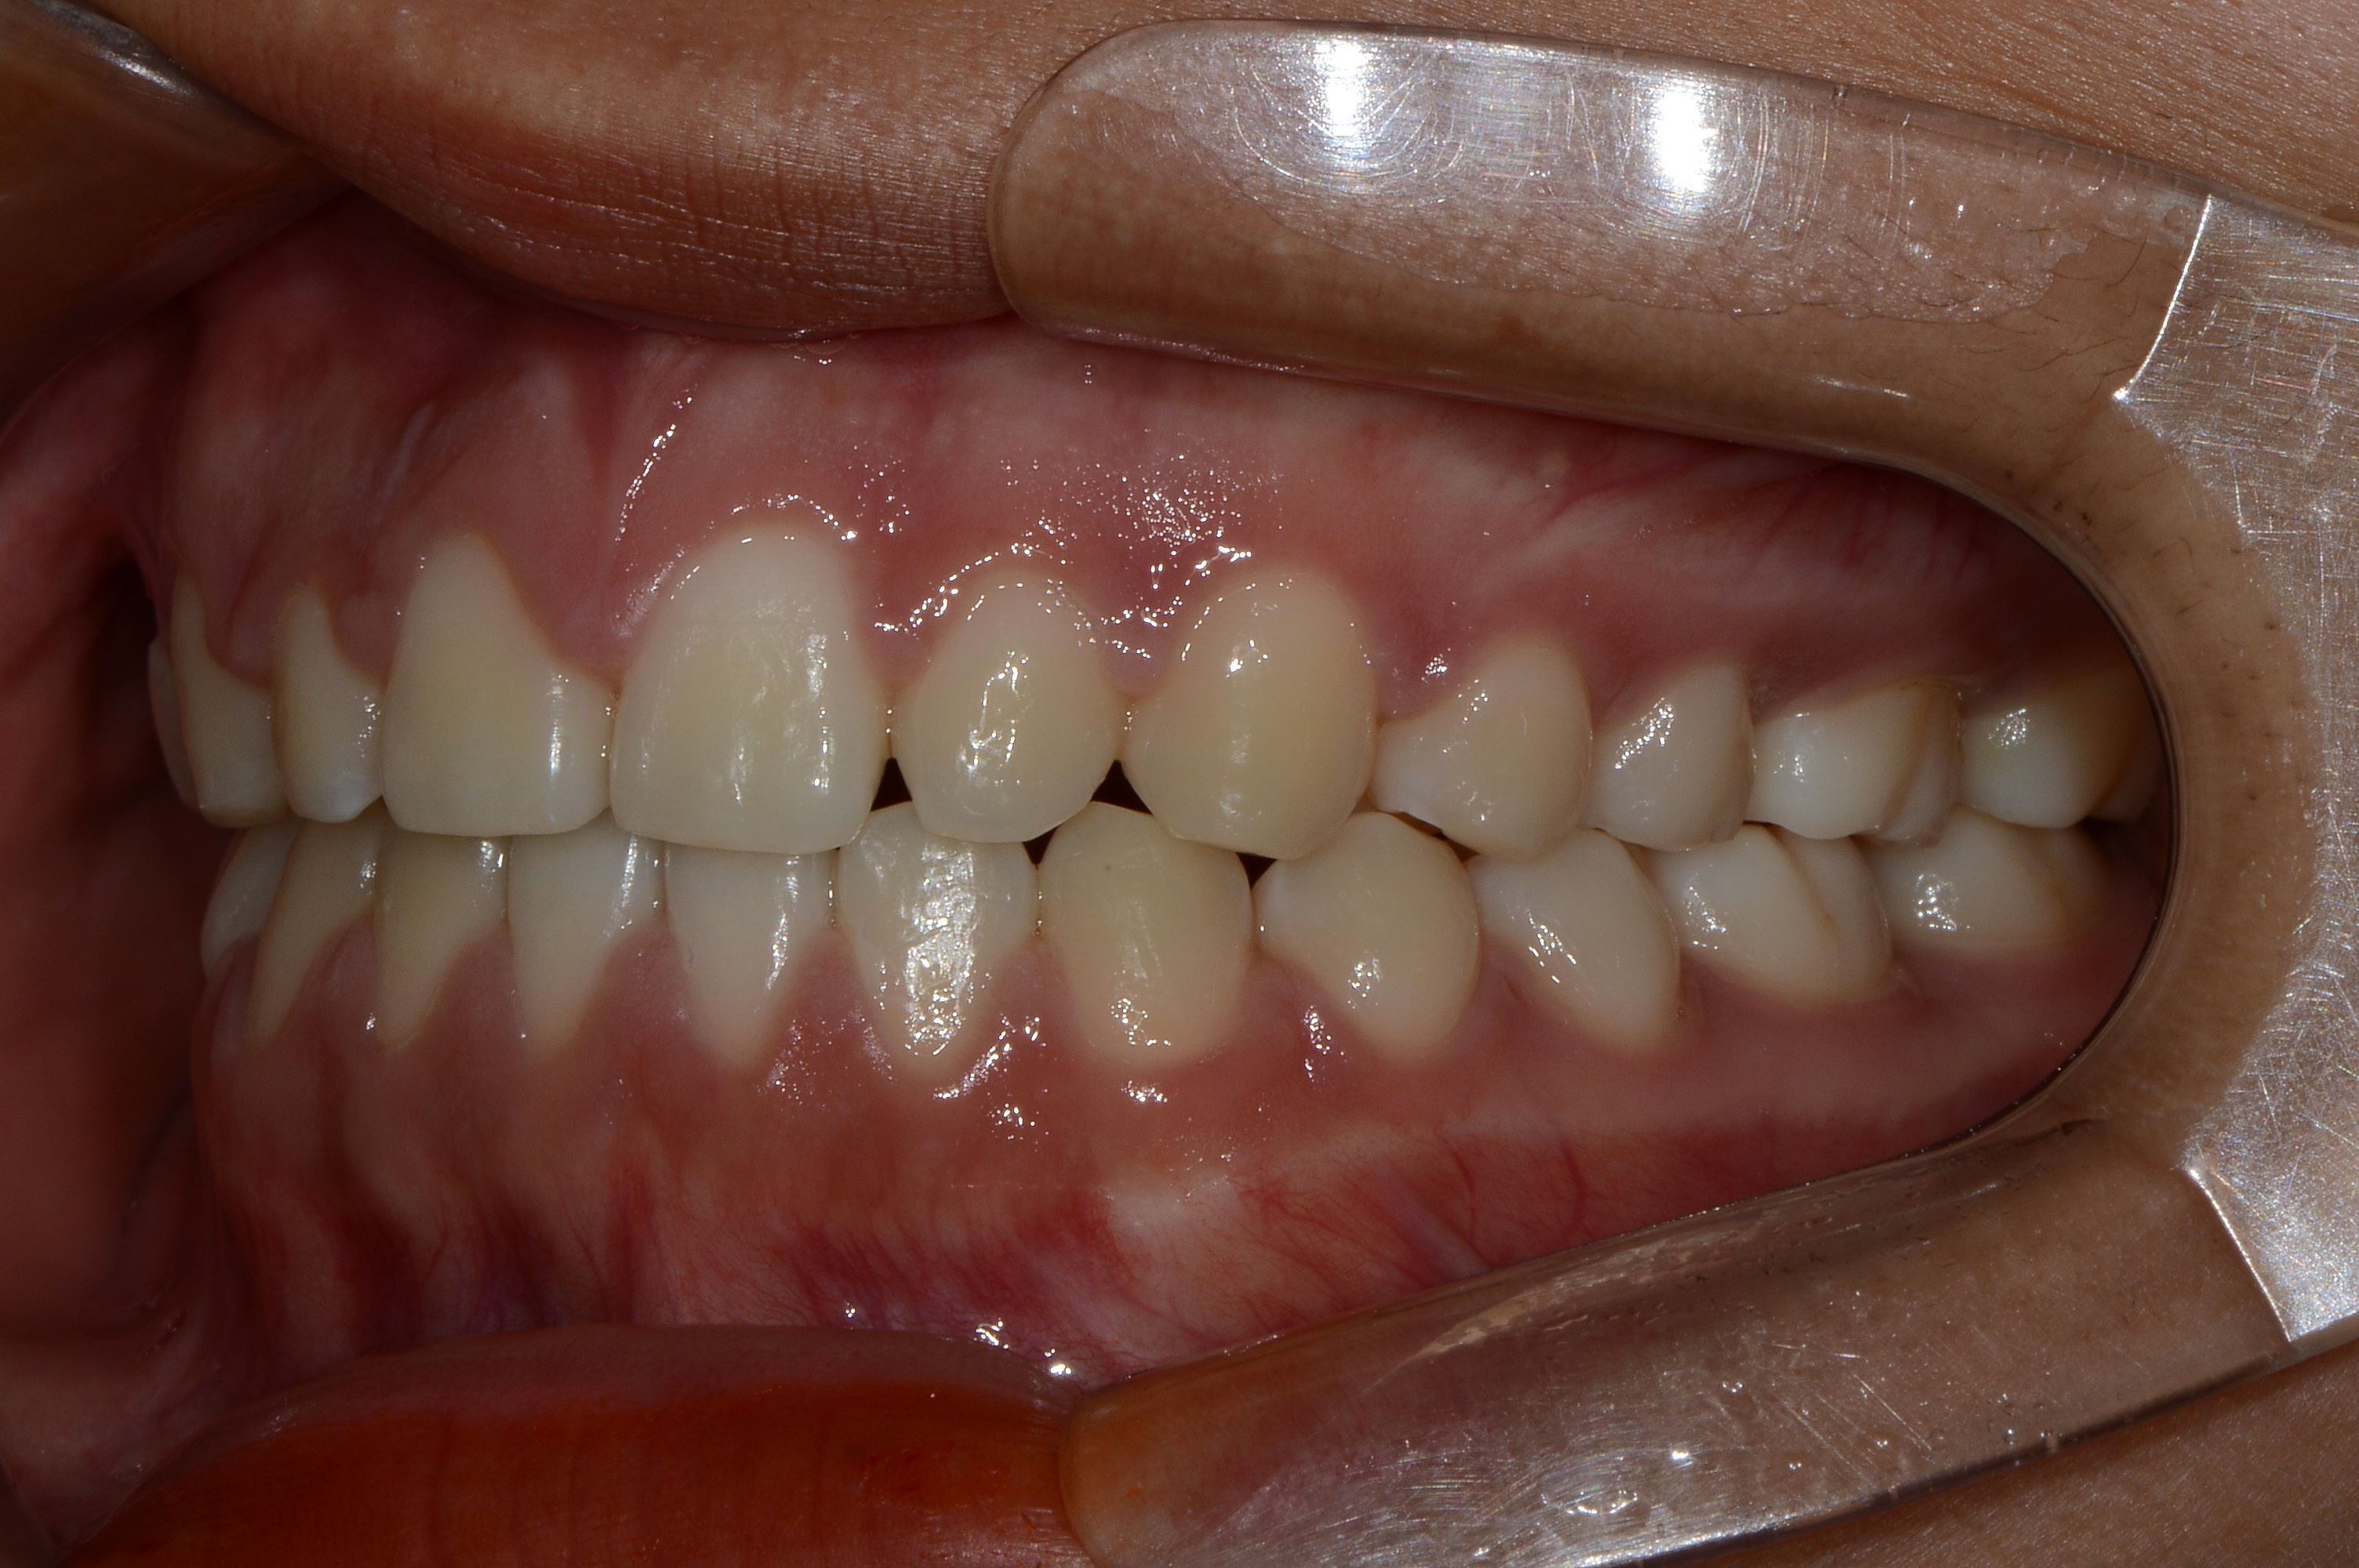

치료 후 사진입니다.